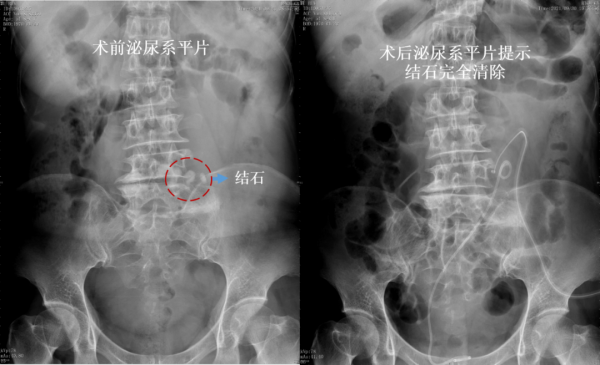

在李建興指導下,由胡衛國主刀在超聲引導下,透過腹壁一步步找到腹腔內異位的腎臟和腎內結石,再透過超聲探頭擠壓腹壁,將腎臟前方的腸管等組織推開,避免誤傷。反覆探查確認後,在組織縫隙內選定安全穿刺通道,對融合腎腎盂結石區域進行精準穿刺,一針見尿。胡衛國繼續使用球囊,順利擴張建立手術通道,應用經皮腎鏡將結石粉碎並清除。用時1小時20分鐘,手術順利結束。

術後,張女士恢復順利,第1天就能夠順利排氣,下地活動。複查X線和CT顯示,不僅結石完全被清除,而且臟器保護良好,沒有出現腹腔內臟器和血管損傷,腹腔內積液、尿漏等手術併發症等。10天后,張女士順利出院。